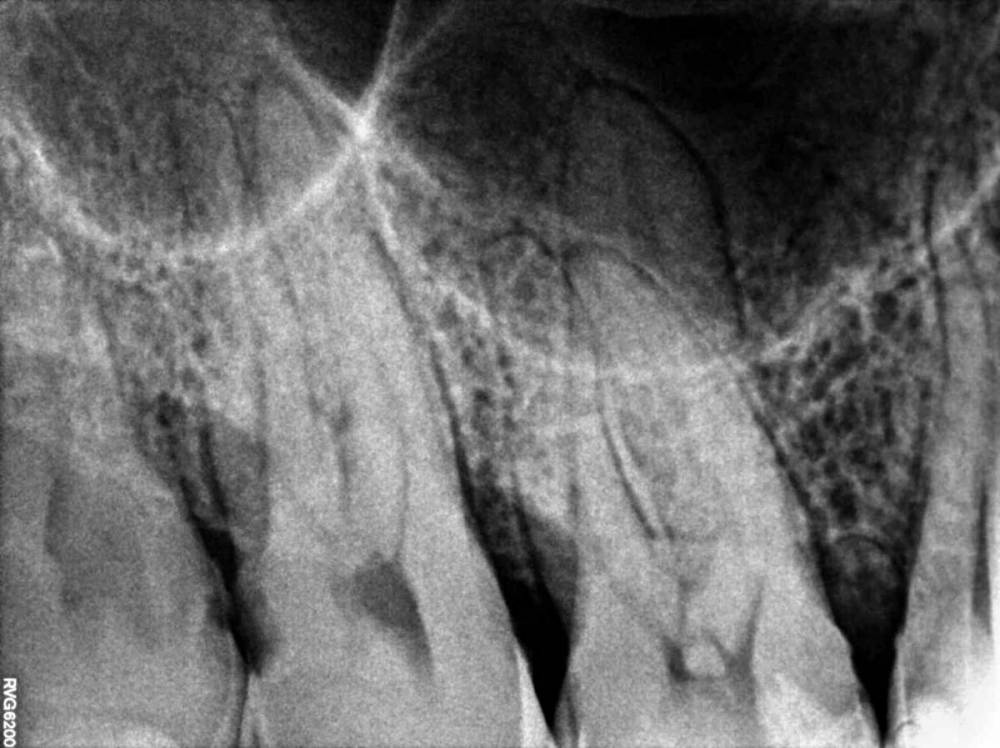

Jyuly Опубликовано 30 мая, 2023 Поделиться Опубликовано 30 мая, 2023 Добрый день! 4 года назад установила керамическую вкладку E-MAX на "живой" зуб (предлагали на выбор пломбу или вкладку, как более долговечный и надежный вариант). 4 месяца назад вкладка начала "гулять", терапевт осмотрел, сказал, что она треснула + кусочек небольшой откололся. Была у ортопеда в марте, он сказал после осмотра и свежей ортопанорамы от февраля этого года (свежего прицела не было) что, велика вероятность, зуб придется депульпировать. Скажите, пожалуйста, можно ли по снимку сказать (одному из них 2 года, другому точно не знаю, ~3-4) степень вероятности депульпирования зуба? Что это за "шарик" внутри? Несколько дней, как зуб начал беспокоить, точнее, не сам зуб, а выше, челюсть ноет, отдает в область глаза и уха. Может, это и не от этого зуба боли, между 7 и 8 кариес по снимкам. Хороший терпевт, которого мне посоветовали, в отпуске до 29 июня, я и не понимаю, какого специалиста мне искать спешно - терапевта, для пломбирования каналов или ортопеда для установки новой вкладки. Помогите, пожалуйста, просто крик души! Москва Ссылка на комментарий

Carioznik Опубликовано 31 мая, 2023 Поделиться Опубликовано 31 мая, 2023 (изменено) 1 час назад, Jyuly сказал: Здравствуйте! Нет, не замечала. Понаблюдаю ещё сегодня. Наклон головы в любую сторону? И о чем это может говорить? В любую. О пульпите из-за этого "шарика". Но это редкое явление, так что, не заморачивайтесь по этому поводу. Это так... профессиональный интерес. И к вашему случаю, похоже, не имеет отношения Изменено 31 мая, 2023 пользователем Carioznik 1 Ссылка на комментарий

Jyuly Опубликовано 2 июня, 2023 Автор Поделиться Опубликовано 2 июня, 2023 31.05.2023 в 10:37, Carioznik сказал: В любую. О пульпите из-за этого "шарика". Но это редкое явление, так что, не заморачивайтесь по этому поводу. Это так... профессиональный интерес. И к вашему случаю, похоже, не имеет отношения И всё же, что это за шарик может быть?))) Я понаблюдала, боль не усиливается при наклоне. Полностью перестала жевать на этой стороне - и боль стала беспокоить меньше. Ссылка на комментарий

Carioznik Опубликовано 2 июня, 2023 Поделиться Опубликовано 2 июня, 2023 2 часа назад, Jyuly сказал: что это за шарик может быть? Дентикль 1 1 Ссылка на комментарий